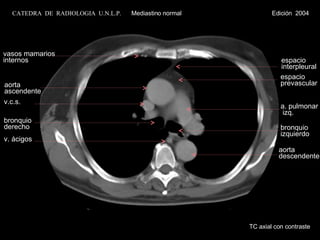

aorta ascendente v.c.s. v. ácigos espacio prevascular a. pulmonar izq. bronquio derecho bronquio izquierdo aorta descendente espacio interpleural vasos mamarios internos TC axial con contraste CATEDRA  DE  RADIOLOGIA  U.N.L.P.   Mediastino normal  Edición  2004

aorta ascendente v.c.s.v. ácigos espacio prevascular a. pulmonar izq. bronquio derecho bronquio izquierdo aorta descendente espacio interpleural vasos mamarios internos TC axial con contraste CATEDRA DE RADIOLOGIA U.N.L.P. Mediastino normal Edición 2004